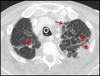

What pathology is seen here? What are the arrows pointing to?

Pulmonary Embolism (PE) Red arrows: Areas with less signal